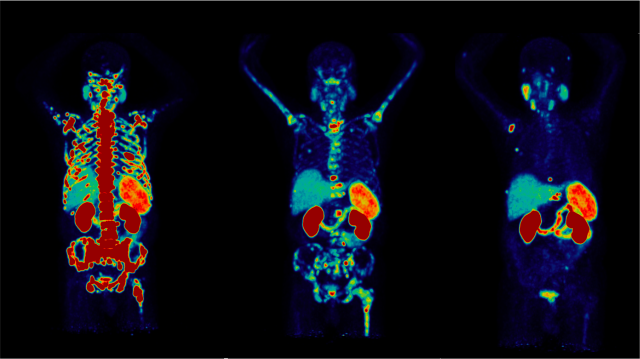

PET Imaging and Therapeutic Targeting of PSMA

Three medical scans showing skeletal and organ structures in different poses.

Together with the University of California, San Francisco (UCSF), we introduced prostate-specific membrane antigen (PSMA) PET/CT imaging in the United States, an approach which has changed the landscape of prostate cancer imaging for the better. This technique is now widely available across the country.

Building upon this success, our team completed the first Phase II clinical trial (RESIST-PC) to investigate the safety and efficacy of 177Lu-PSMA-617 for prostate cancer therapy, and were key contributors to the Phase III clinical trial (VISION). The FDA subsequently approved 177Lu-PSMA-617 (Pluvicto) for the treatment of PSMA-positive prostate cancer.